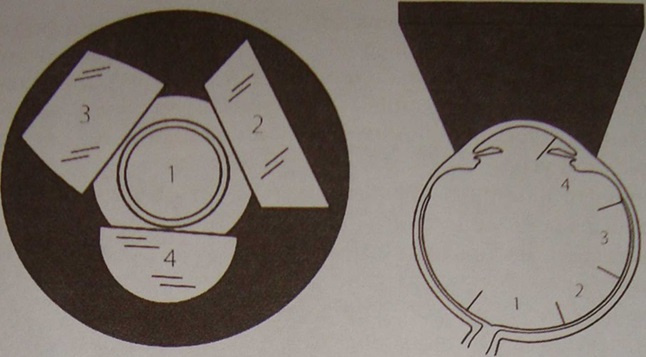

By the way, for inspection, you need to use not a flashlight, as is done in most clinics, but special lenses for examining the fundus. There is a universal contact lens — Goldman's lens. This flat lens with a system of three mirrors is very widely used in the examination and laser coagulation of the anterior segment of the eye and retina.

顺便说一句,进行检查时,您不需要像大多数诊所那样使用手电筒,而是需要使用特殊的镜片检查眼底。 有一个通用隐形眼镜-高盛镜头。 这种带有三面镜系统的平面透镜非常广泛地用于检查眼和视网膜的前段并进行激光凝结。

In each mirror, we see different parts of the retina, and, turning it clockwise, we get complete information. Something like this:

在每个镜子中,我们都可以看到视网膜的不同部分,顺时针旋转它可以获取完整的信息。 像这样:

And this is the scheme in which mirror which department of the eye we inspect:

这是我们检查哪个眼部的方案: